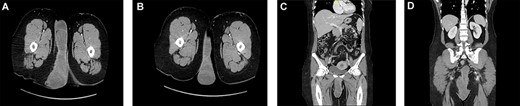

Multiple cuts of a CT abdomen and pelvis scan showing a multicompartmental, multilobulated, low pelvic and perineal soft-tissue lesion, with heterogeneous enhancement, measuring almost 21 × 17 × 5 cm.

A 42-year-old anemic female presented to the clinic, complaining of a recurrent obturator hernia for the past 10 years. It was a large, painless, progressive swelling in the perineum, involving the labial fold. There were no bowel obstruction symptoms. She was previously operated for the hernia three times in different centers. On examination, there was a large swelling extending from the right medial gluteal area to the right labial fold measuring 20 × 15 cm. It was nontender and had a firm consistency, with no overlying skin changes (Fig. 1). Laboratory investigations were within normal limits. Computed tomography (CT) scans of the abdomen and pelvis showed a massive, multicompartmental, multilobulated soft-tissue lesion in the lower pelvis and perineum, exerting a mild mass effect (Fig. 2). Perineal mass excision, possible mesh placement and stoma creation was planned. At exploratory laparotomy, the abdominal and pelvic cavities were examined. There was no evidence of a defect or hernia. The extraperitoneal space was explored and the obturator foramen was identified without any hernia. The procedure then shifted to excision of the mass. It was lobulated within a capsule and extending from the vulvar commissure to the anus. It was also involving part of the lateral vaginal wall, the lower part of the rectum and anal canal which needed to be excised (Fig. 3). The mass was directly subdermal at the vulvar commissure site, so part of the labia minora skin was excised with the mass. The vaginal wall was repaired by a urogynecologist. The rectum was repaired by the primary surgeon. A diversion end sigmoid colostomy was created. Wound closure was assisted by plastic surgery. No tissue or skin coverage was required. The histopathological report revealed an AA extending to the margins with ulcerated and reactive skin tissue. Immunostaining for estrogen and progesterone were both positive. The postoperative course was uneventful. At 8 months follow-up, abdomen and pelvis CT concluded that there was a minimal residual perineal mass without extension to the pelvis. Following discussion in the multidisciplinary tumor board, she was started on hormonal therapy after ~1 year of surgery with leuprolide 22.5 mg, intramuscular, every 3 months. Hormonal therapy was continued for a total of 15 months with frequent follow-up images which showed no change in the residual mass. She underwent colostomy reversal 3 years after and was doing well on regular follow-ups. The patient consented to the publication of this case report with images. All measures were taken to ensure her privacy and anonymity.